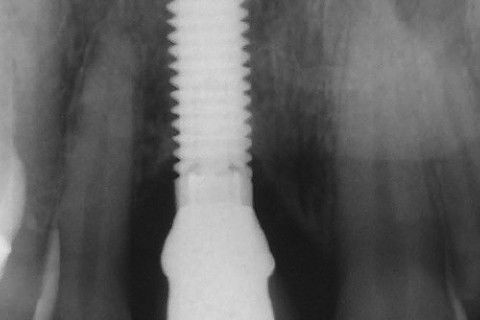

Radiografia inicial

Paciente com fratura do elemento 11. Como havia grande perda óssea vestibular, optamos por fazer implante primeiramente a extração do dente e após 4 meses a colocação do implante. Concomitante 'a colocação do implante, enxerto óssseo + membrana para regeneração óssea foi colocado e aguardamos 6 meses para então fazermos a reabilitação com coroa metalo-ceramica parafusada.